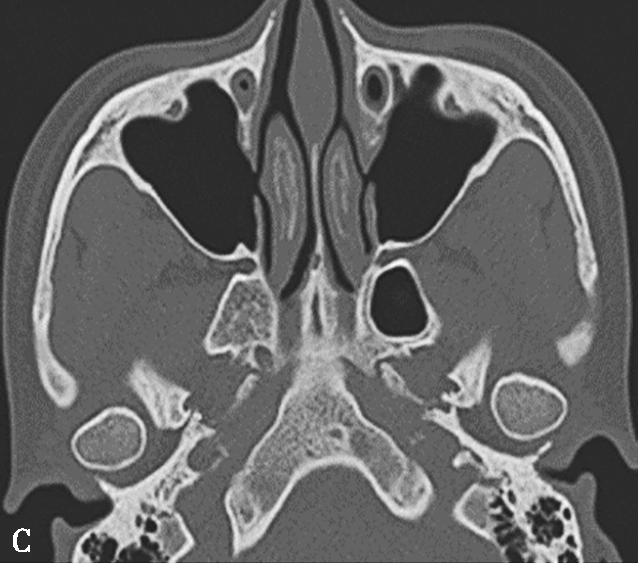

鼻丘气房位于筛漏斗的前上部,与泪骨、上颌骨、筛骨、额骨、鼻骨关系密切。是由筛漏斗直接发展而来。鼻丘气房通常位于额窦底的前部,构成额隐窝的前壁,大小不一,过大、过多可妨碍额窦引流,引起额窦炎。鼻丘气房和钩突眶内壁附着点之间的关系非常密切。当钩突与眶内壁没有附着点时,鼻丘气房不存在;当钩突与眶内壁仅有一个附着点时,鼻丘气房存在;当钩突与眶内壁有两个及以上附着点时,形成上下两个气房,在冠状面观察,偏下的气房称为鼻丘气房,偏上的气房称为额气房,两者内壁均由钩突构成(图1-3-1)。

图1-3-1 鼻丘气房及额气房CT解剖

A~C.鼻丘气房(五角星),额气房(星),钩突(白箭),筛骨纸板(箭头)